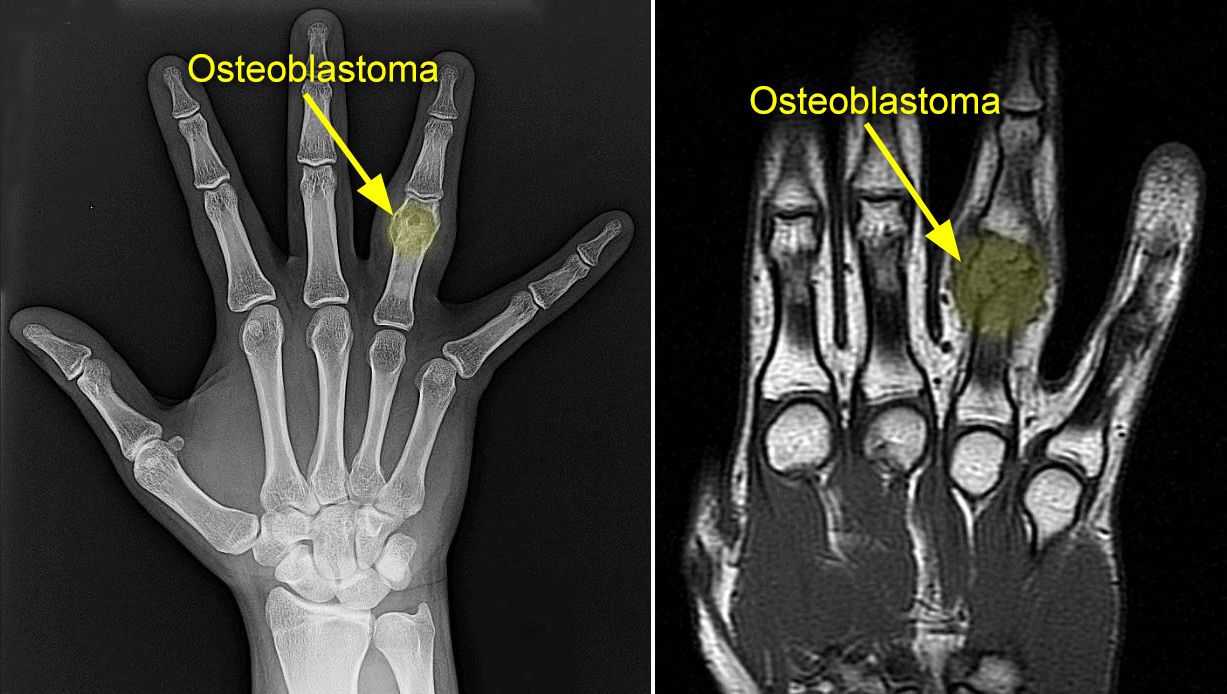

You also may feel stiffness or tenderness in the bone. The most common symptom of bone cancer is pain, which is caused by either the spread of the tumor or the breaking of bone that is weakened by a tumor. Bone cancer signs are mostly not visible at the beginning, and its cause may be an entirely different medical condition. Bone cancer can affect any bone, but most cases develop in the long bones of the legs or upper arms. Primary bone tumors are relatively rare after the fourth decade of life and less frequent as compared to chondromas affects tubular bones of the hands and feet in 50% of cases.

Foot Cancer Q A Foot Ankle Specialists from www.newtownpodiatry.com Still, if these problems go on for a long time without a known reason, you. Cancer can happen anywhere in the body, even the bones. Inflammation and tender joints can also be a sign of bone cancer. Cancer in the bones of the spine can press on nerves, causing numbness and tingling or even weakness. Bone cancer can affect any bone, but most cases develop in the long bones of the legs or upper arms. While bone cancer signs differ by the bones affected, most bone cancers have several symptoms in common. Complete information about bone cancer, including signs and symptoms; Enchondroma usually appears in bones of your hands and feet.

Whether primary or metastatic, cancer in the bones may present with symptoms such as increasing pain, swelling and/or a more sudden intense pain. For example, if someone has lung cancer that has spread to bone, the cells of the cancer in the bone still look and. Signs and symptoms of bone cancer include bone cancers are broken down into separate types based on the type of cell where the cancer began. People who have undergone bone marrow transplantation may also be at higher risk of developing bone cancer. Note the time when any symptoms first appear. Bone pain can cause a dull or deep. Bone tumors can be of two different types. Here we cover the common signs of bone cancer. When cancer starts, it transforms healthy cells into malignant cancer cells that grow out of control. These symptoms are more often due to conditions other than cancer, such as injuries or arthritis. Enchondroma usually appears in bones of your hands and feet. How is bone cancer diagnosed? Primary bone cancer develops in the bones.